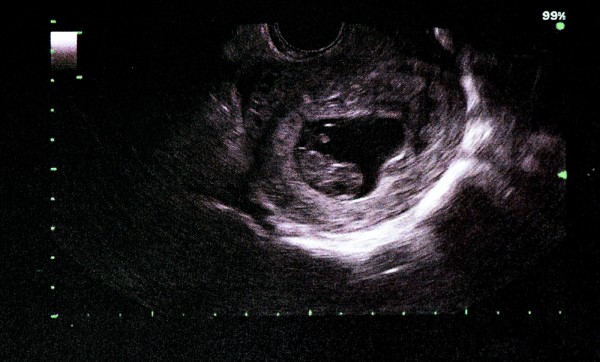

Узи

На девятой неделе беременности ультразвуковое исследование рекомендуется для выявления возможных аномалий у плода и уточнения срока беременности. Хотя плановое УЗИ не является обязательным, женщина может пройти его по своему желанию.

Во время процедуры врач заметит увеличение матки и наличие плодного пузыря. На экране будущий малыш выглядит как крошечный человечек, однако на этом этапе специалист еще не может определить его пол. Датчик также фиксирует сердцебиение плода, которое составляет около 130 ударов в минуту.

У мальчиков уже сформированы яички, но они пока находятся в брюшной полости, поэтому на УЗИ невозможно определить пол ребенка.